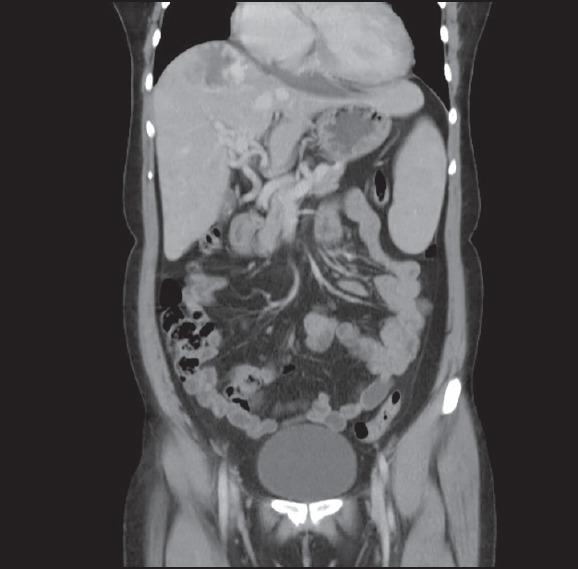

A 44-year-old woman came with complaints of recurrent episodes of hematemesis and epistaxis. Patient had a family history of similar complaints. Patient underwent esophagogastroduodenoscopy (EGD), which revealed telangiectasia in the stomach. Imaging of the abdomen showed features suggestive of arteriovenous shunting.

一名44岁女性因反复呕血和鼻出血前来就诊。患者有类似症状的家族史。患者接受了食管胃十二指肠镜检查(EGD),结果显示胃部有毛细血管扩张。腹部影像学检查显示有动静脉分流的特征。